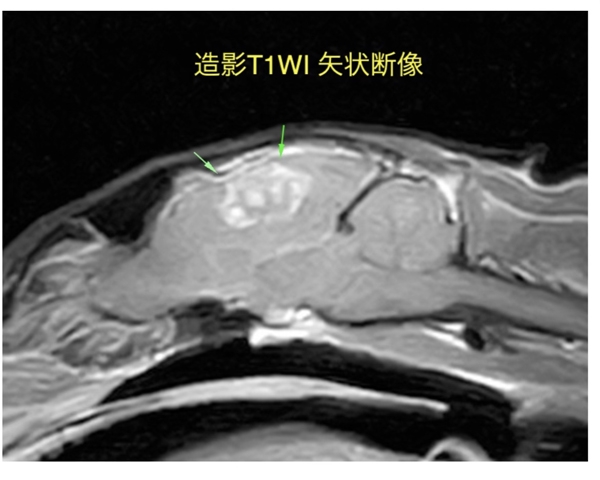

先日、福岡市西区にありますルカどうぶつ二次診療クリニックさんで行われた

猫ちゃんの脳腫瘍摘出手術に、藁戸先生が麻酔医として参加してきました!

普段から、MRI検査が必要な患者様はこちらのクリニックの

神経科、柴田先生にご紹介させて頂いており、大変お世話になっています!

今回は猫ちゃんの脳外科という珍しい手術ということもあり、

藁戸先生が麻酔に参加させて頂き、力を合わせて手術を実施してきました!!